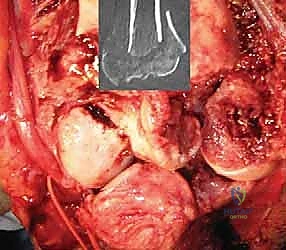

3. إزالة العظام المحطمة وتحضير القناة العظمية

بمجرد الوصول إلى المفصل، يتم تقييم حجم الدمار. تُزال الشظايا العظمية المفتتة التي لا يمكن إنقاذها. بعد ذلك، يتم تحضير القناة الداخلية لعظم العضد (من الأعلى) وعظم الزند (من الأسفل) باستخدام أدوات قياس دقيقة جداً لضمان تطابق المفصل الصناعي مع تشريح المريض.

الصور الشعاعية الإضافية والنتائج داخل غرفة العمليات

يحرص الأستاذ الدكتور محمد هطيف على التوثيق الشعاعي الدقيق أثناء وبعد العملية للتأكد من الموضع المثالي للمفصل.